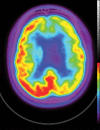

Neurodegenerative diseases are a devastating group of disorders that can be difficult to accurately diagnose. Although these disorders are difficult to manage owing to relatively limited treatment options, an early and correct diagnosis can help with managing symptoms and coping with the later stages of these disease processes. Both anatomic structural imaging and physiologic molecular imaging have evolved to a state in which these neurodegenerative processes can be identified relatively early with high accuracy. To determine the underlying disease, the radiologist should understand the different distributions and pathophysiologic processes involved. High-spatial-resolution MRI allows detection of subtle morphologic changes, as well as potential complications and alternate diagnoses, while molecular imaging allows visualization of altered function or abnormal increased or decreased concentration of disease-specific markers. These methodologies are complementary. Appropriate workup and interpretation of diagnostic studies require an integrated, multimodality, multidisciplinary approach. This article reviews the protocols and findings at MRI and nuclear medicine imaging, including with the use of flurodeoxyglucose, amyloid tracers, and dopaminergic transporter imaging (ioflupane). The pathophysiology of some of the major neurodegenerative processes and their clinical presentations are also reviewed; this information is critical to understand how these imaging modalities work, and it aids in the integration of clinical data to help synthesize a final diagnosis. Radiologists and nuclear medicine physicians aiming to include the evaluation of neurodegenerative diseases in their practice should be aware of and familiar with the multiple imaging modalities available and how using these modalities is essential in the multidisciplinary management of patients with neurodegenerative diseases.©RSNA, 2020.